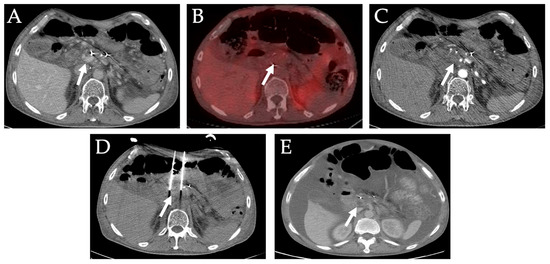

7. Primary and Metastatic Adrenal Tumors

- Donlon, P.; Dennedy, M.C. Thermal ablation in adrenal disorders: A discussion of the technology, the clinical evidence and the future. Curr. Opin. Endocrinol. Diabetes Obes. 2021, 28, 291–302. [Google Scholar] [CrossRef]

- Yamakado, K. Image-guided ablation of adrenal lesions. Semin. Interv. Radiol. 2014, 31, 149–156. [Google Scholar] [CrossRef] [Green Version]

- Shaikh, J.; Raymond, A.; Somasundaram, A.; Loya, M.F.; Nezami, N. Novel Protocol for CT-Guided Percutaneous Ablation of Hyperplastic Adrenal Glands in Cushing Syndrome. CardioVascular Interv. Radiol. 2022, 45, 1–12. [Google Scholar] [CrossRef] [PubMed]

- Rosiak, G.; Milczarek, K.; Konecki, D.; Otto, M.; Rowinski, O.; Zgliczynski, W. Percutaneous Bilateral Adrenal Radiofrequency Ablation in Severe Adrenocorticotropic Hormone-dependent Cushing Syndrome. J. Clin. Imaging Sci. 2020, 10, 60. [Google Scholar] [CrossRef] [PubMed]